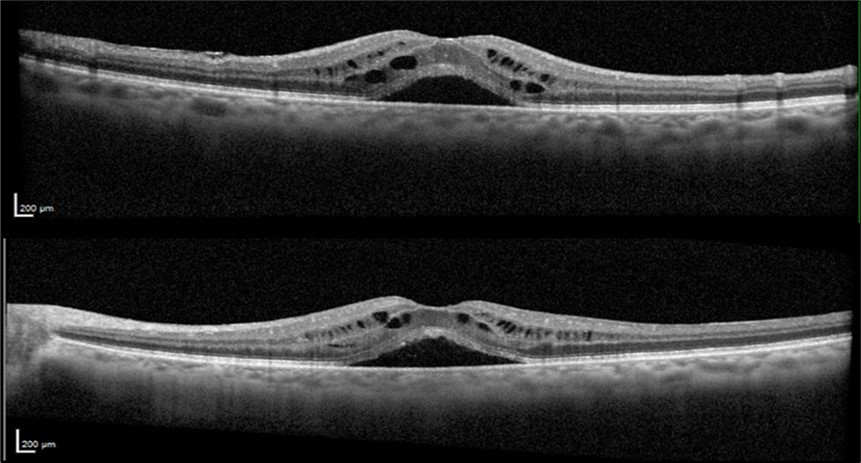

The patient was closely monitored every three months during the first year following the discontinuation of Leflunomide, and then every six months thereafter. Follow-up evaluations included repeated VA tests, fundus examinations, and SD-OCT imaging to assess the resolution of CME and any improvements in visual function. After two years of discontinuing Leflunomide, the CME resolved without recurrence and without the need for any topical treatment. At her final visit, VA was OD 20/25 and OS 20/25. OCT OU revealed resolution of the CME with a dry fovea (Figure 4).

Figure 4.Optical coherence tomography of both eyes revealing the sustained resolution of the cystoid macular edema after Leflunomide discontinuation.

Optical coherence tomography of both eyes revealing the sustained resolution of the cystoid macular edema after Leflunomide discontinuation.